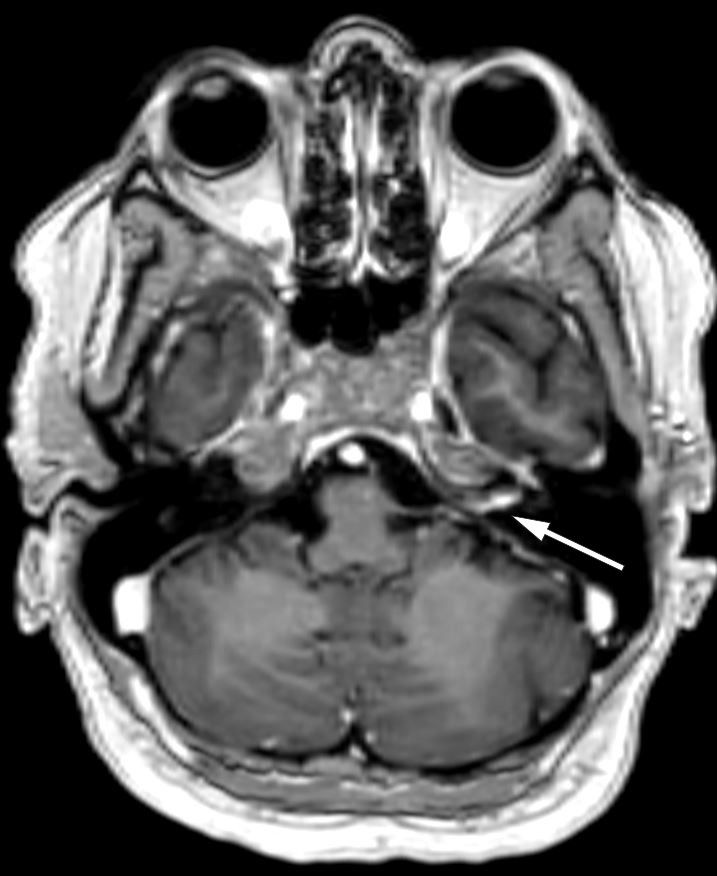

Tre dager senere ble pasienten reinnlagt grunnet forverring av svimmelhet og kvalme. Ny MR av hodet viste tegn til inflammasjon, med økt kontrastoppladning i indre øregang og langs facialisnervens tympaniske og mastoide segment på venstre side (T1-vektede bilder) (figur 2) og økt signal i indre øregang i både cochlea og vestibularisapparatet på venstre side (FLAIR SPIR-sekvenser). Videonystagmoskopi med kalorisk testing viste 56 % svakere respons på venstre side, som tegn på redusert funksjon i vestibularisnerven. Det ble bemerket et kløende, papuløst utslett i hodebunnen. Dette var en sannsynlig bivirkning av valaciklovir.